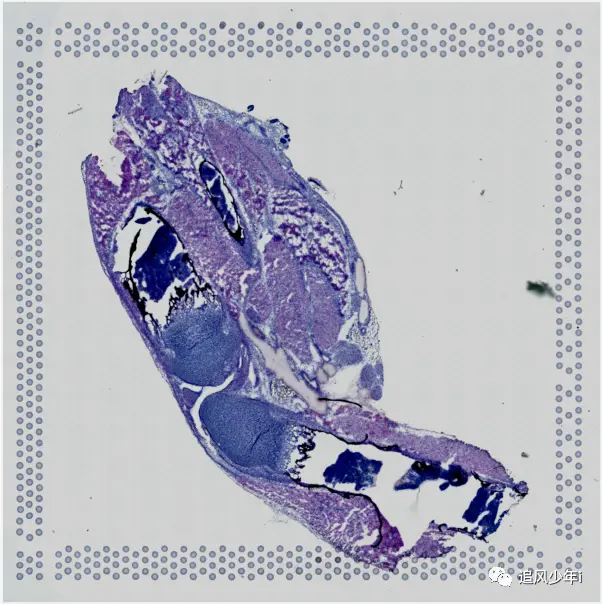

相信大多数还是利用Seurat来进行联合分析,如果用了其他软件,可以将联合的矩阵结果进行替换,我们还是以之前的结果为例,HE染色和单细胞空间联合分析的结果部分展示如下

好了,我们要开始了,一定要记住,前面的单细胞空间联合要亲自做